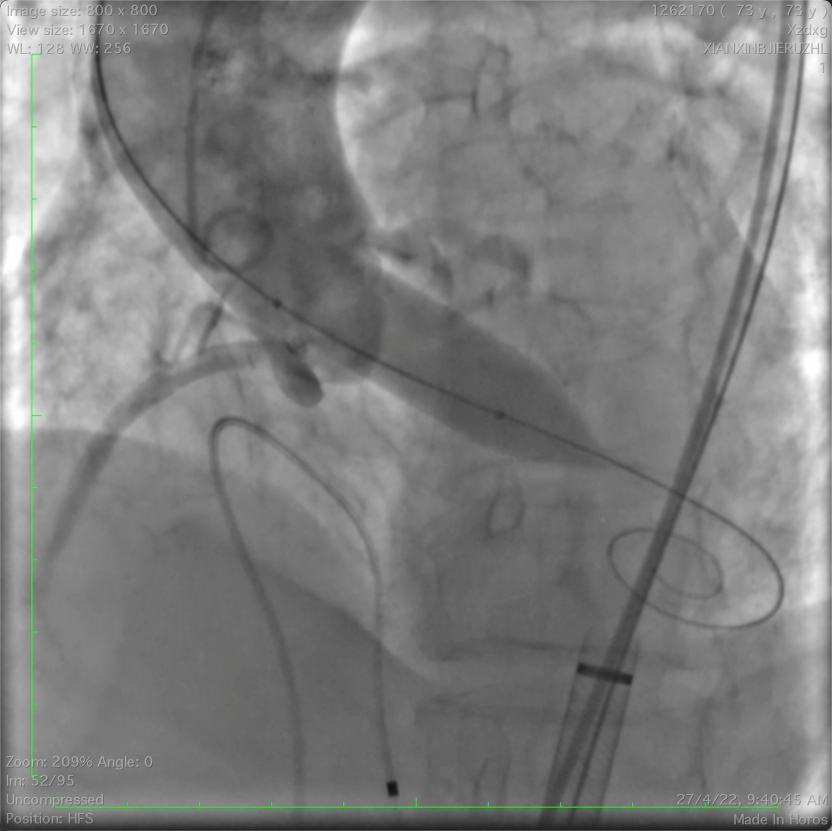

左冠植入4.0x19mm冠脉开窗支架

图片

5.0mm球囊后扩张支架近段

复查左冠开口面积恢复至12.76mm2

经主动脉路径植入14mm-16mm PDA封堵器